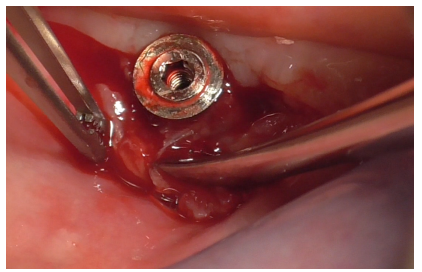

A healing abutment was then screwed into the implant to preserve the connection during subsequent stages (Figure 21).

Figure 21

Additional decontamination was performed with the previously used diamond ball insert for the Ultrasonic Device (Figure 22).

Figure 22